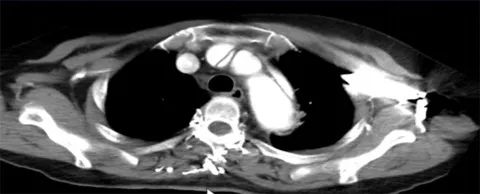

主动脉CTA造影

患者回重症监护室(CCU)后立即行主动脉CTA造影,显示主动脉夹层(Standford A 型),破口位于升主动脉起始部,宽约7 mm;夹层范围为升主动脉至主动脉弓,累及头臂干起始部,右颈总动脉开口。双侧冠状动脉充盈不均匀,内可见低密度阴影。

根据造影结果,诊断考虑主动脉夹层累及双侧冠状动脉,右侧明显,1小时后病人不幸去世。